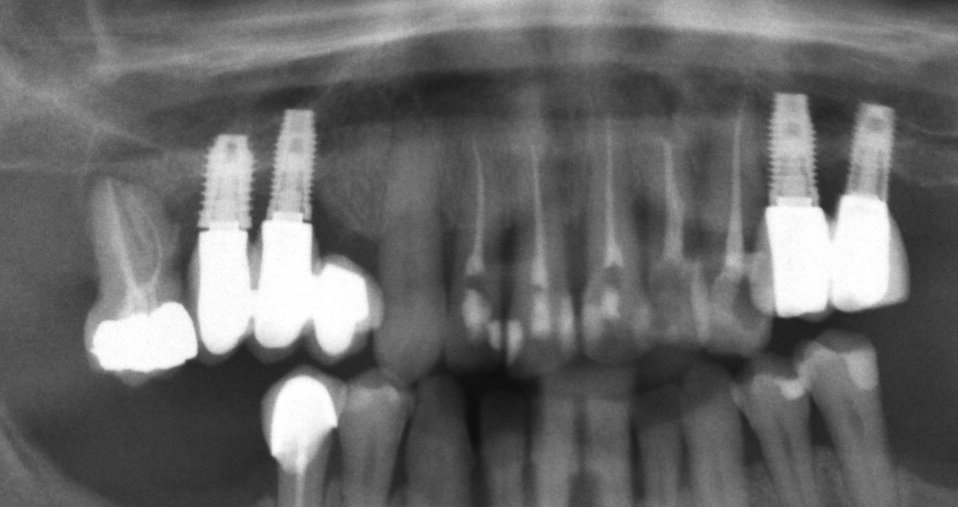

buenas tardes compañeros, me podriaid ayudar con la marca de estos implantes? muchas gracias por vuestra atencion, 1 saludo

Como cirujano de una de la clinicas que colaboro me mandan esta rx para determinar que implantes lleva en el primer cuadrante para poder realizar la rehabilitacion protesica de nuevo.